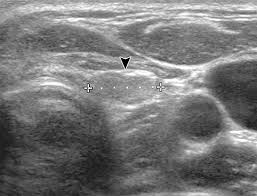

When evaluating a patient with a thyroid nodule, assessment of the lymph nodes, particularly in the lateral neck, provides important clues regarding the malignancy risk. In addition, the following tests may be used to diagnose head and neck cancer: Optimal positioning and exposure of the neck for ultrasound of the thyroid and parathyroid glands (a, b) and lateral neck for lymph node examination and mapping (c).while the vast majority of patients are supine on the exam table with a pillow supporting the shoulders to allow gentle neck extension, keep in mind that some patients have beautiful anatomy (d) that allows ultrasound exam even in. A biopsy can be performed in cases where ultrasound cannot differentiate benign from malignant tumours. Before the node starts the lesions even very experienced specialist, the device will be able to register an increase, its contour irregularity, violation of the structure.

Ultrasoundis very sensitive and showsmany nodules that cannot be felt. In addition, the following tests may be used to diagnose head and neck cancer: Ultrasound does not show the structures inside joints, dr. Fna might also be used in patients whose cancer has been treated by surgery and/or radiation therapy, to help find out if a neck mass in the treated area is scar tissue or if it's a return (recurrence) of the cancer. Ultrasound technology cannot find ulcers, but other types of diagnostic tests can. Some research explores the potential for finding ulcers with an ultrasound, but experts do not have enough data to recommend it. The path report states loose fragments of poorly differentiated malignant epithelial cells with enlarged hyperchromatic irregular nuclei and apoptosis are seen in a hemorragic background that includes few scattered atypical keratinized squamous cells. Testing lymph nodes the lymph nodes in the neck are often the first place cancer cells spread to outside the primary site. Ultrasoundimaging is a noninvasive medical test that helps physicians diagnose and treat medical conditions. If this lump is of concern then a biopsy would be the next step. Cancer of the liver or fatty. Optimal positioning and exposure of the neck for ultrasound of the thyroid and parathyroid glands (a, b) and lateral neck for lymph node examination and mapping (c).while the vast majority of patients are supine on the exam table with a pillow supporting the shoulders to allow gentle neck extension, keep in mind that some patients have beautiful anatomy (d) that allows ultrasound exam even in. Abnormal enlargement of the spleen.

Confirming that a lump in the neck is developing from the thyroid or connected tissue. The sonographer then gently presses the transducer against the side of your neck. Identification of a suspicious lymph node increases the likelihood of cancer and may warrant fna of the node in lieu of the thyroid (see fig. Surgical levels of the neck. This test will usually help determine that the nodule has a low chance of being cancerous (has characteristics of a benign nodule), or that it has some characteristics of a cancerous nodule, and therefore a biopsy is indicated. The ultrasound technician (sonographer) may position your head to better access the side of your neck. During a physical examination, the doctor feels for any lumps on the neck, lips, gums, and cheeks. Abnormal enlargement of the spleen. In my experience an ultrasound won't tell you if you have cancer, it just shows a lump. If cancer is found in a lymph node, you may need a neck dissection or other additional treatment. Doctors often use ultrasound to guide a needle to do a biopsy (taking out fluid or small pieces of tissue to be looked at under a microscope). Throat cancer is often easily seen by an ent exam. It can detect abnormal tissues, growths, and cysts and give a suspicion of cancer based on how those images look.